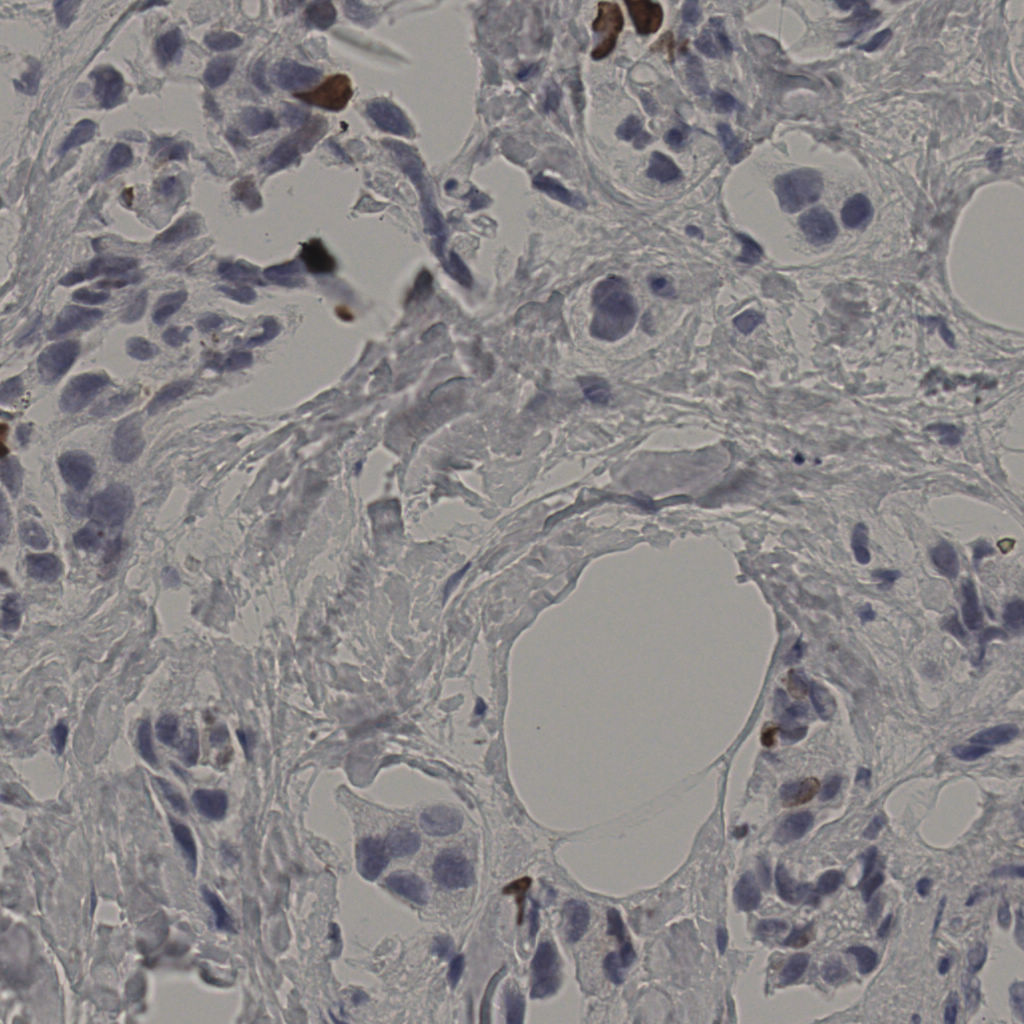

标记后

标记前